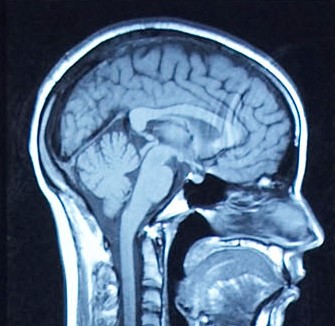

Brain Health Awareness Week: October 15-19

Brain scanResearchers, clinicians, patients and members of the general public are invited to take part in Brain Health Awareness Week from October 5-19, hosted by the University of Ottawa Brain and Mind Research Institute, in collaboration with The Ottawa Hospital and other partners.

Activities will include public lectures on topics such as spinal cord and brain regeneration, neuromuscular disease and ALS, decoding brain circuits, predicting Parkinson's disease and caring for the aging brain.